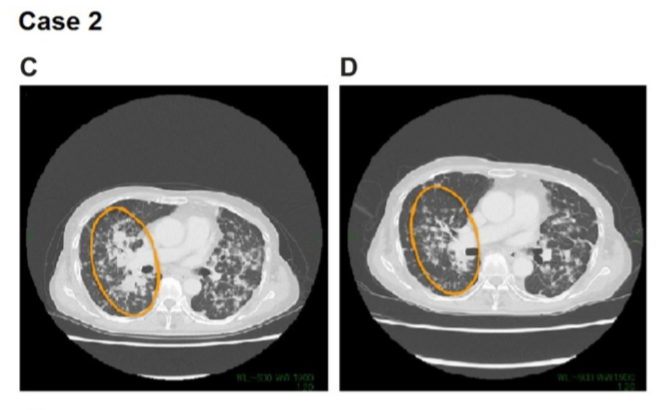

案例2

患者2是62岁亚洲女性,从不吸烟,2015年被诊断为转移性非粘液性肺腺癌,确诊时已有多处肺和淋巴结转移。在用阿法替尼治疗前,患者接受过4线治疗,对使用过的治疗方案的最佳反应都是达到病情稳定(SD)。

在各治疗手段治疗都出现进展下,通过测序检测,发现患者有CD74-NRG1融合。患者因此使用上了阿法替尼,在接受阿法替尼治疗11个月后,患者于2018年11月达到PR。截止到2020年2月统计时,患者仍在使用阿法替尼,持续PR中。

总体而言,上述两例报告中,我们均观察到多线治疗后的肺腺癌患者,通过阿法替尼的治疗,有超过24个月的持续治疗效果,比前期报道的PR持续时间长达12个月还要好。